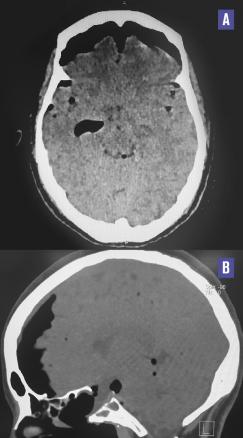

Cette femme de 38 ans consultait pour des céphalées en casque évoluant depuis une semaine. La patiente précisait avoir une rhinorrhée antérieure depuis une intervention neurochirurgicale sur adénome hypophysaire réalisée un mois auparavant. L’examen ne notait ni atteinte des paires crâniennes ni céphalée orthostatique. La patiente était apyrétique et son bilan biologique ne montrait pas de syndrome inflammatoire ou infectieux. Une liquorrhée cérébrospinale était visualisée au contact du sphénoïde à la rhinoscopie. La tomodensitométrie cérébrale était normale (fig. 1 ). La patiente était hospitalisée et, le soir même, chutait dans la salle de bains. Une nouvelle tomodensitométrie (48 h après la première) montrait une pneumencéphalie diffuse témoignant d’une brèche méningée (fig. 2 ). La chute a probablement accentué la brèche, occasionnant la pneumencéphalie secondaire.

La chirurgie hypophysaire par voie trans-sphénoïdale est la technique de référence pour les tumeurs hypophysaires. Une rhinorrhée post-opératoire est rapportée dans 0,5 à 6 % des cas.1 Elle expose le patient a une méningite, une pneumencéphalie ou une hypotension intracrânienne chronique, évoquée sur le caractère orthostatique des céphalées. L`analyse de la rhinorrhée avec dosage de la bêta-trace (protéine spécifique du liquide cérébrospinal) permet d’orienter le diagnostic. Devant toute rhinorrhée post-opératoire associée à des céphalées une brèche méningée doit être recherchée.